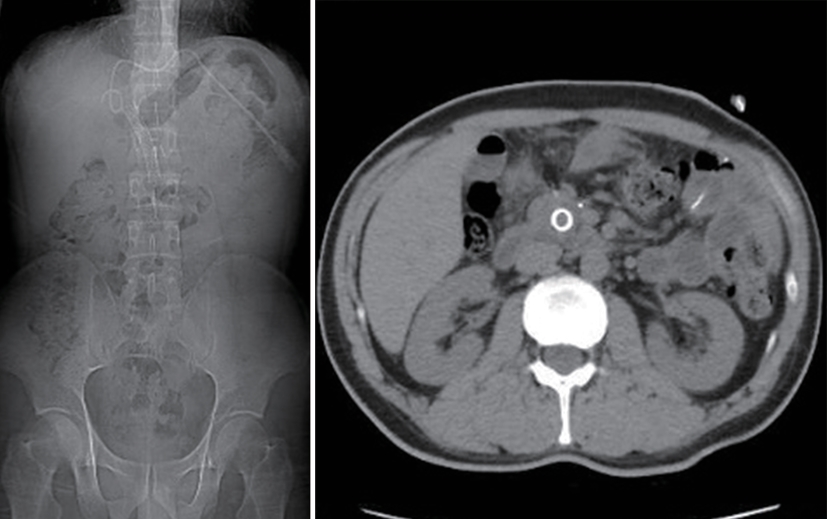

• Duodenum-preserving pancreatic head resection, also known as Beger surgery, has a high incidence rate of bile duct injury after surgery, while the treatment modality for bile duct injury depends on the severity of the injury, and endoscopic therapy is often challenging in case of severe bile duct injury. Recently a patient with biliary fistula after Beger surgery was admitted to Affiliated Hangzhou First People’s Hospital, Westlake University, and successful diagnosis and treatment were achieved through oral choledochoscopy-assisted percutaneous-endoscopic rendezvous technique.